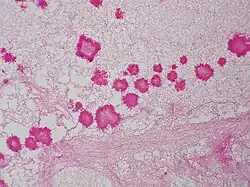

The diagnoses of geotrichosis cannot be determined without using culture or microscopic measurements.[5] The laboratory diagnosis of geotrichosis involves collected fungi samples areas of infections without contamination.[6] Scraping of the mouth lesions and the ulcers can provide a sample of G. candidum. Samples can also be collected from pus and mucus can be obtained from the feces.[5] Sputum can be searched for the mucoid-like white flakes for further examination.[6][5] Culturing the cylindrical barrel-shaped or elliptical fungi in considerable numbers in oral lesions is an indicator that a patient may have geotrichosis.[6] Under the microscope the fungi appears yeast-like and septate branching hyphae that can be broken down into chains or individual arthrospores. Arthrospores appear rectangular with flat or rounded ends.[3][5] Under the microscope the arthroconidia size range from 6-12μm x 3-6μm. Arthroconidia and coarse true hyphae can be observed can be observed under the microscope.[3] Another identification method for G. candidum is selective isolation method. A selection isolation method based on the fungi tolerance to novobiocin and carbon dioxide can determine if G. candidum is the cause of illness.[2]